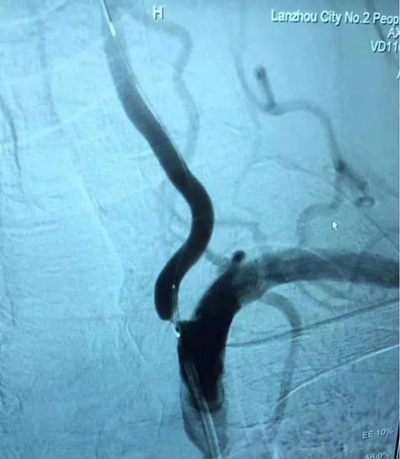

术前:左侧椎动脉起始部重度狭窄